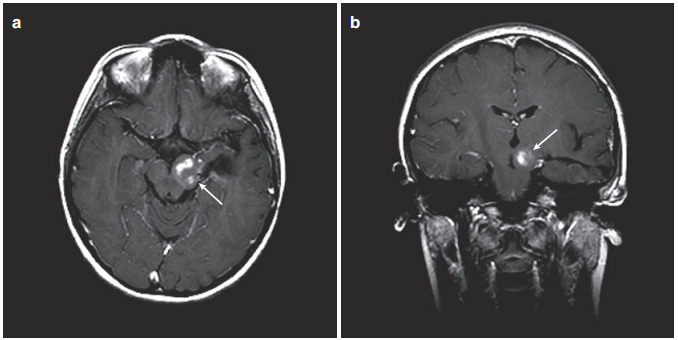

图4。患儿术后MRI,(a)轴位增强MRI显示肿瘤少量残留在左侧被盖。(b)冠状MRI对比显示从颞中回至中脑肿瘤的少量残余肿瘤。

术后2周未出现新的神经功能障碍,患儿只出现了一过性记忆障碍且较快恢复,术后生长和智力发育正常。但由于肿瘤仍有残余,Rutka教授与团队多次内部讨论,考虑到患儿的年龄、肿瘤残余情况、既往病史等因素,为Luke制定了专属化疗方案,事实证明,患儿对此方案耐受情况良好。后续资料显示其在随访期间继续接受化疗,但Luke已无需进一步的手术治疗,这让他的家人高兴。

局灶性脑干胶质瘤治愈率高吗?Rutka教授在这则病例中总结道:手术的目的是在保护神经功能情况下较大水平的切除肿瘤。患有局灶性中脑肿瘤的儿童在的神经外科切除肿瘤后可以表现得好。如果术后有残余肿瘤并继续进展,那么对于年龄较大的儿童来说,有靶向化疗、常规化疗或放射治疗等选择。通过较大水平的顺利切除手术,大多数患有局灶性中脑肿瘤的儿童可以过上正常的生活。鉴于复发的可能性,强烈连续MR复查。总体而言,患有局灶性中脑肿瘤的儿童预后良好,5岁生存率为90%或更高。